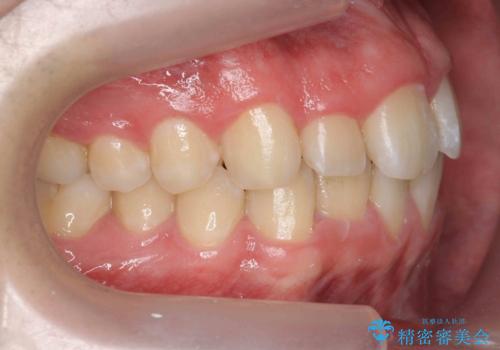

- 前歯のすきまと八重歯を主訴に来院。

左上の乳犬歯が残っており、その下から生えてくるはずの犬歯(永久歯)が左上小臼歯部に萌出していました。

左上の乳犬歯は根もしっかりしていたため、

➀そのまま矯正する。乳歯がいずれダメになったときにそこはブリッジかインプラントを検討する

②乳歯は抜歯し、ブリッジかインプラントを矯正後に入れる

を提案し、➀を選択されました。

将来的にインプラントは希望されないとのことだったため、乳歯の部分は隙間を開けてインプラントを入れる用のすき間を確保するということは特に行いませんでした。

乳歯をそのまま並べたため、上顎の左右の犬歯の幅は非対称になっています。